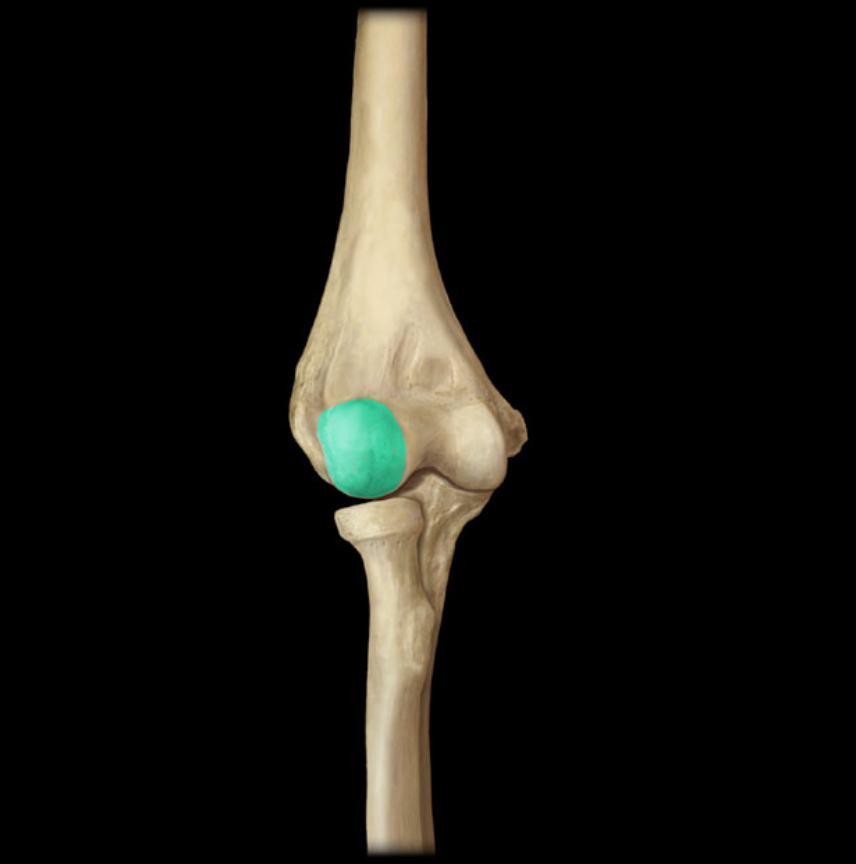

Capitulum of humerus